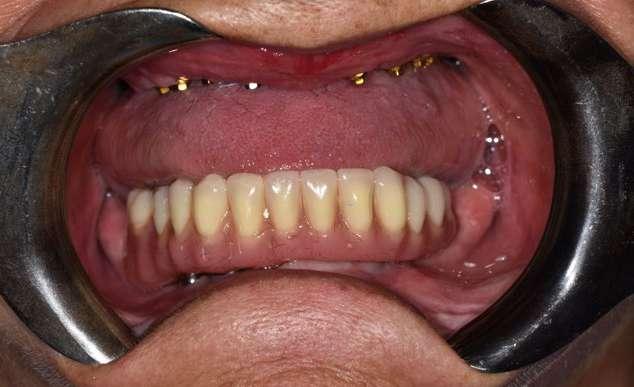

Figuras 3-6. Imágenes de un caso de prótesis atornillada en molar unitario inferior. Vemos el estado de los tejidos blandos gingivales tras la segunda fase y colocación del transepitelial unitario y la radiografía. En las imágenes inferiores (5 y 6) observamos el caso a los 4 años y 10 años de seguimiento, con estabilidad completa de los tejidos óseos peri-implantarios.

Figuras 7-10. En las dos imágenes superiores (7 y 8) observamos la realización de la prótesis cementada mediante un bioplilar fresado a la altura gingival con la radiografía antes del cementado de la corona. En las imágenes inferiores (9 y 10) vemos la prótesis a los 7 años de seguimiento y a los 9 años transformada en una prótesis atornillada al perderse la pieza anterior al implante y realizarse un puente con el nuevo implante. En este caso, el nivel óseo permanece estable con el paso del tiempo.